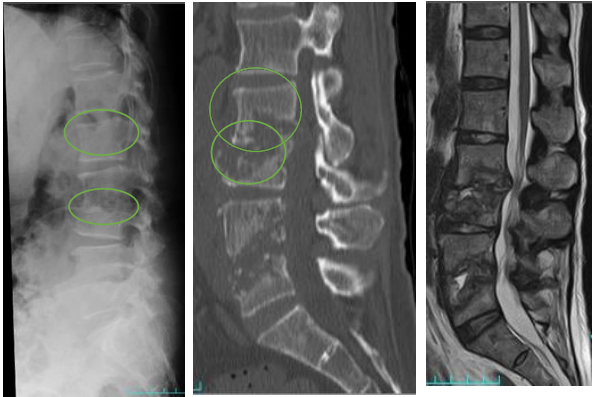

#腸腰筋膿瘍/椎体椎間板炎/化膿性脊椎炎

これらの疾患は合併することも多く、並列した疾患の概念として捉えています。発熱、体動困難、腰痛などの主訴で疑いますが、高齢者では臓器特異的な主訴を訴えないことも多いです。逆に肺炎像や膿尿も認めない発熱患者さんでは意識して診察を行います。脊椎叩打痛や腸腰筋兆候(Psoas sign)を確かめます。起因菌は黄色ブドウ球菌・CNSが約半数を占めます。CTでは腸腰筋の左右差や椎体の終板が破壊されていないかを確認します。椎体椎間板炎や化膿性脊椎炎の確定診断にはMRIが必要です。

急激な経過をとる事は少ない印象の疾患ですが、急性の経過や進行を辿る例や神経症状を伴う例では硬膜外膿瘍を疑う必要があります。

(引用:日本脊髄外科学会より。)終板(椎体の端の高吸収な領域)が壊されてるかどうか確認